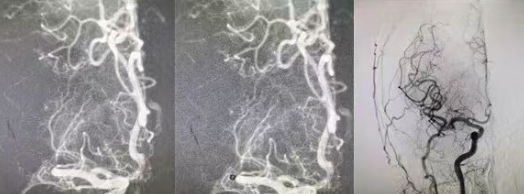

首都医科大学附属北京安贞医院孙铁男教授到国文医院指导完成多台高难度冠脉介入手术

为全面精进国文医院心血管疾病介入诊疗体系建设,让区域内心血管疾病患者足不出域即可享国家级顶尖医疗资源。近日,国内心血管内科领域“第一梯队”——首都医科大学附属北京安贞医院心内科孙铁男教授,在国文医院出诊、手术、查房、会诊疑难心血管疾病患者,并指导开展高难度冠脉介入手术,为本地区心血管健康事业发展注入强劲动力,给广大心血管疾病患者带来健康福祉。 阅读量:328